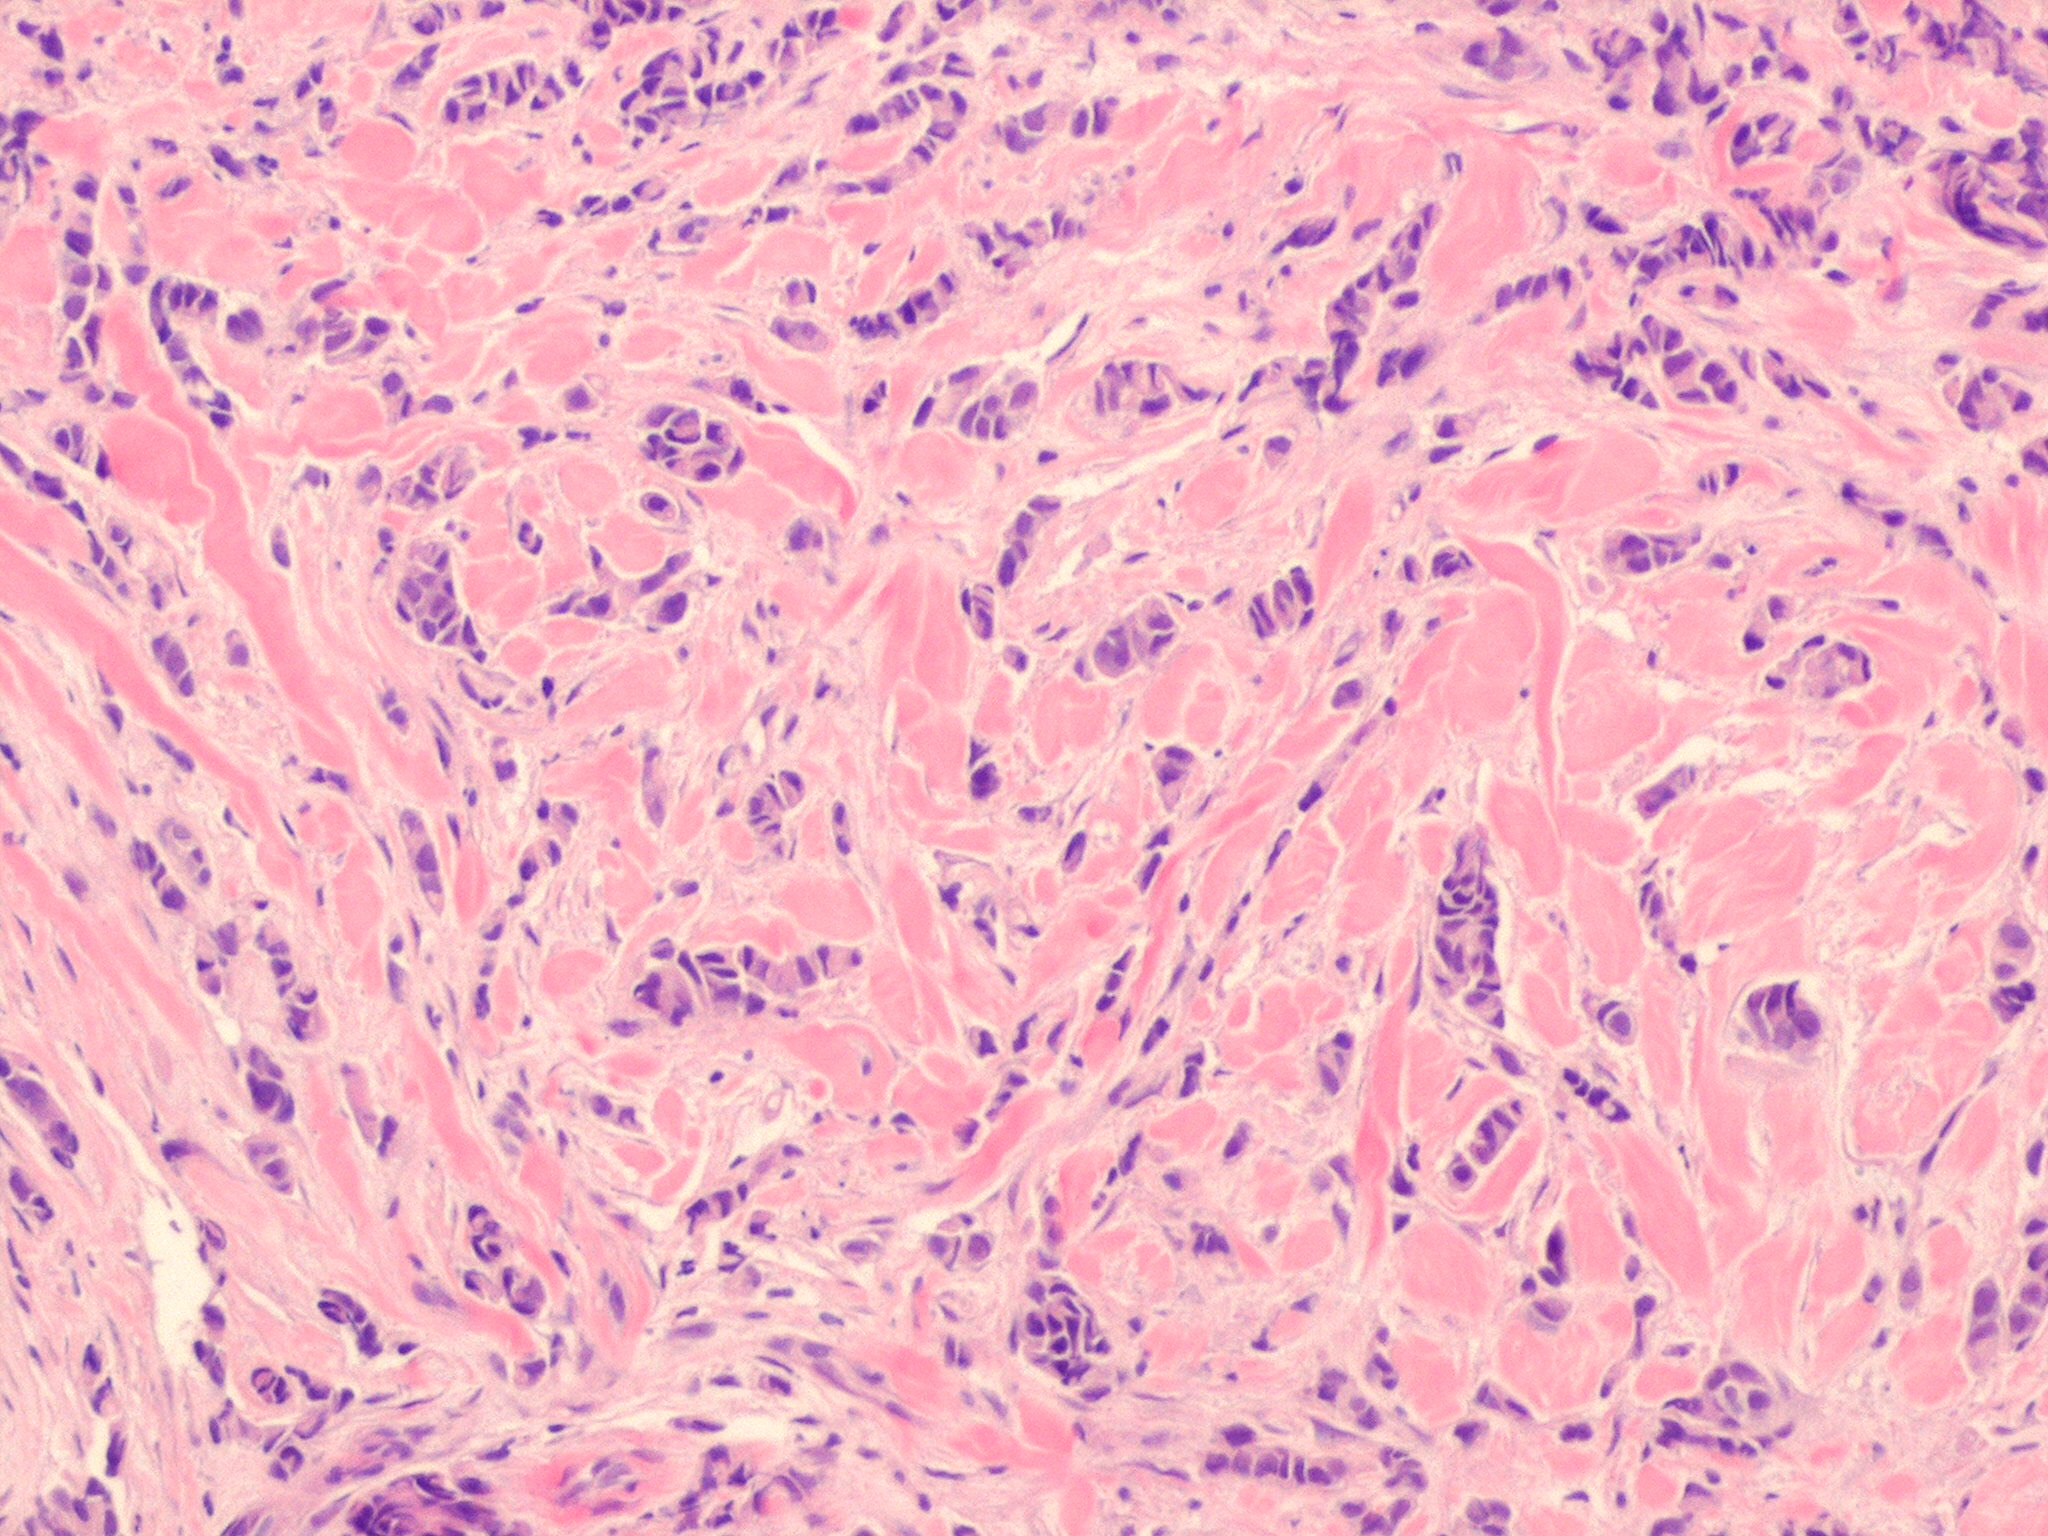

metastasis